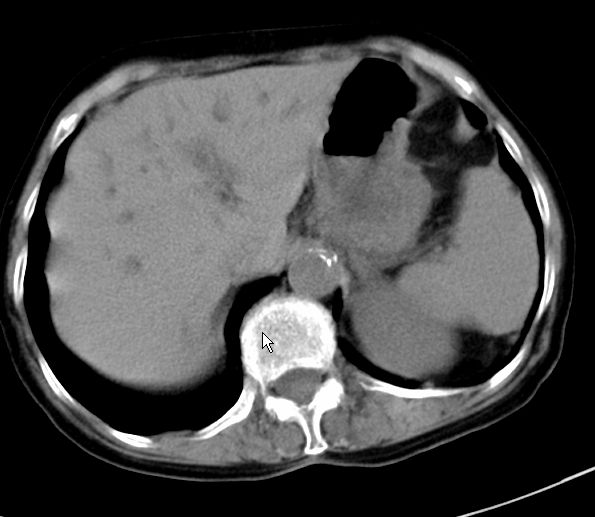

以下是引用zjzjr在2008-12-16 12:49:00的发言:[br]肝内外胆管全程扩张,胆囊明显增大,未见占位征像.建议mrcp.

以下是引用jiangjing在2008-12-16 13:19:00的发言:[br]肝内外胆管全程扩张,胆囊明显增大,扩张胆总管下段径较中上段小,未见胰管扩张,提示胆总管远端梗阻伴感染.建议增强及mrcp 检查

以下是引用朱亮在2008-12-16 12:54:00的发言:[br]胆总管远端应薄层扫描 胆总管逐渐变细 考虑胆系慢性炎症